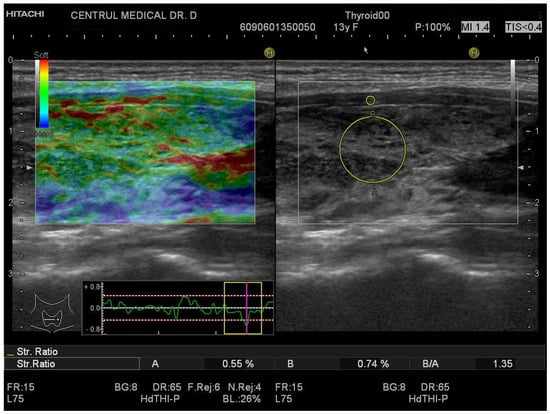

2.4. Conventional Ultrasound and Elastography Examination

3.1. Strain Elastography Measurements

3.2. SWE Measurements